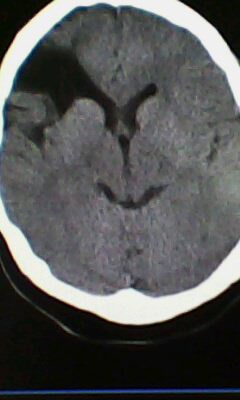

标题: CT25171:患者间断性头痛 无外伤史 [打印本页]

标题: CT25171:患者间断性头痛 无外伤史

右侧额叶脑穿通畸形囊肿。

图不清,有灰质异位吗?与脑裂畸形鉴别

右侧额叶脑穿通畸形囊肿。支持!